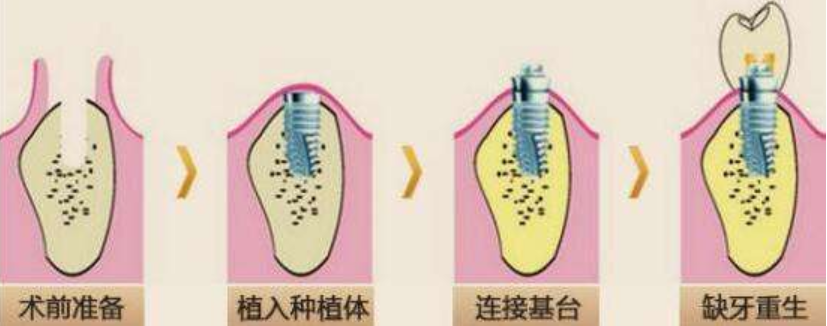

01ЪѕЧАзМБИ

жжжВбРГнжЎЧАЃЌПкЧЛМьВщБиЪЧВЛПЩЩйЕФВНжшЃЌВщПДПкЧЛЕФОпЬхЧщПіЃЌбРВлЙЧУмЖШЁЂСкбРЕФбРжмзщжЏЁЂбРЬхзщжЏМАИљМтЕШЧщПіЁЃ

ШЛКѓЃЌвНЩњЛсбЏЮЪЙЫПЭВЁЪЗЃЌШчЪЧЗёгаИпбЊбЙЁЂЬЧФђВЁЕШЁЃГфЗжЦРЙРЙЫПЭЕФПкЧЛЬѕМўЃЌЮЊЛМепШЋУцХХГ§вўЛМКѓЃЌВХФмНјаажжжВЁЃ

зюКѓвНЩњЛсИљОнИїШЫЧщПіЃЌЩшМЦжжжВЗНАИЃЌШчШЗЖЈжжжВЯЕЭГЁЂжжжВЬхЕФЪ§СПЁЂЮЛжУЁЂЗНЯђЁЂГЄЖШЃЌжЦзїГіжжжВЪжЪѕашгУЕФ3DЕМАхЕШЁЃ

02жВШыжжжВЬх

е§ЪНПЊЪМжжжВбРЪжЪѕЁЃАбЩшМЦКУЕФ3DЕМАхЬздкЛМепПкЧЛФкЃЌдк3DЕМАхЕФ“ЕМКН”ЯТзъвЛИіПзЃЌАбжжжВЬх“Тё”НјШЅЃЌвЛАужжвЛПХашвЊ10ЗжжгЁЃНЋбРЙЧДВФкбЯУмЗьКЯЃЌДѓдМвЛИіаЧЦкКѓПЩвдВ№ЯпЁЃ

03ЕШД§ЙЧНсКЯ

ЕШД§жжжВЬхгыбРВлЙЧНєУмНсКЯЁЃетИіЪБМфЕФГЄЖЬвђШЫЁЂвђжжжВЯЕЭГЖјвьЃЌгааЉМлИёЩдЙѓЕФжжжВЯЕЭГжЛашЕШД§МИИіаЧЦкЁЃЭЈГЃЯТђЂашЕШД§3ИідТзѓгвЃЌЩЯђЂдђаш4ИідТзѓгвЁЃ

04АВзАгњКЯЛљЬЈ

АВзАгњКЯЛљЬЈЃЈПЩвдАбЛљЬЈМђЕЅРэНтЮЊТнУБЃЉЁЃЪЙжжжВЬхДЉГібРіИЃЌЕШД§ШэзщжЏГЩаЮЁЃ

05ЛЛЩЯгРОУЛљЬЈ

дкВюВЛЖр2--3жмКѓЃЌШэзщжЏГЩаЮКѓЁЃвНЩњЛсгУгРОУЛљЬЈЛЛЯТгњКЯЛљЬЈЁЃЁЗЁЗЁЗЭЦМідФЖСЃКРШЗЛФФМвПкЧЛвНдКзіАыПкжжжВбРММЪѕКУЃП

06ХхДїбРЙк

НЋжЦзїКУЕФбРЙкЬздкгРОУЛљЬЈЩЯЃЌздДЫЃЌжжжВбРОЭДѓЙІИцГЩЁЃ